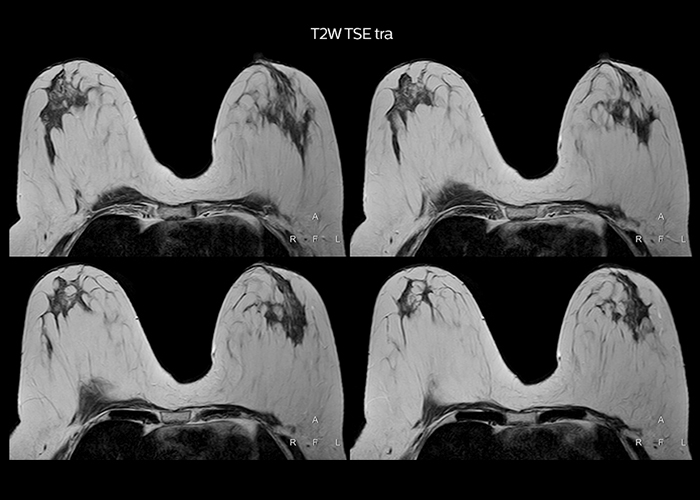

“To avoid coil changes we plan examinations of similar anatomies back to back, such as head and spine. Multiva helps us here a lot because coils don’t need to be changed frequently. Moreover, thanks to parallel imaging technology and 16-channel HeadSpineTorso and 8-channel MSK coils we are able to achieve excellent image quality. In this way Multiva helped us to increase both image quality and productivity.”

“Neurological cases, such as brain and spine imaging, represent the largest share in our MR scanning, followed by musculoskeletal cases. In general, we use simple and basic imaging protocols. But occasionally, we use advanced techniques for problematic cases if necessary.

“Most important, Multiva satisfies our clinical imaging needs very well,” says Mr. Tuna. “Many features of Multiva have become similar to the Ingenia system. Even in more complex imaging such as abdominal and cardiac, the image quality and performance of Multiva is better than we expected. General surgeons and physicians from our hospital’s internal medicine department prefer to refer to us because of this.”